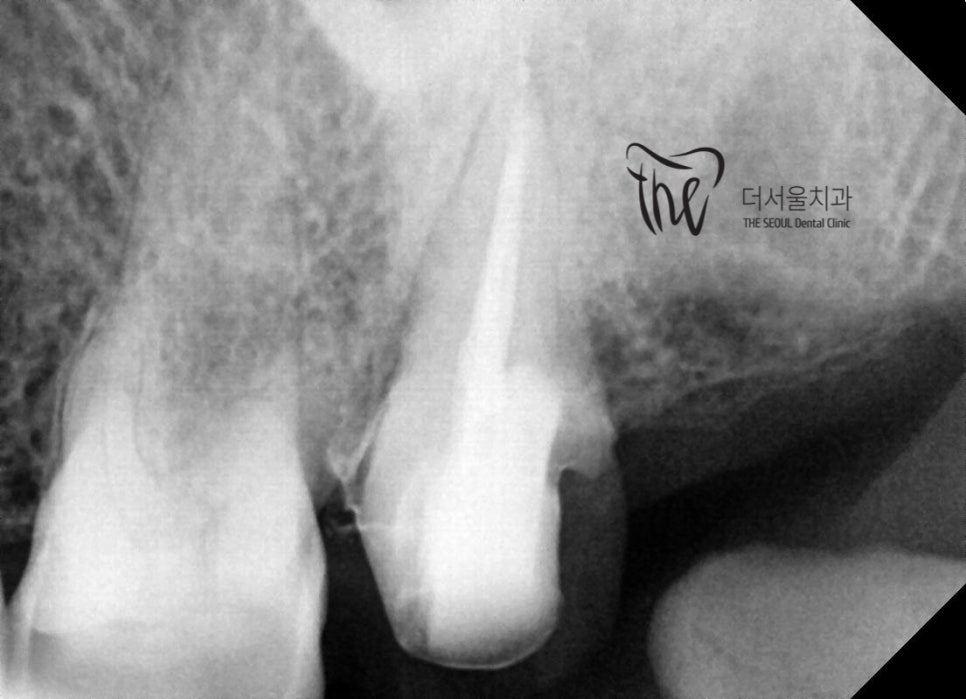

사랑니를 먼저 발치를 한 다음에,

술자가 이제는 측면에서 접근이 가능합니다.

따라서, 클램프 및 러버댐을 건 뒤에

곧바로 충치치료를 진행 한 뒤에 신경치료를

진행하고 있는 사진입니다.

이렇게 하는 이유는, 방습환경을 갖춘다는데

남아있는 치질이 부족해서, 레진 코어 작업 진행

이제, 뿌리 끝까지 신경치료를 끝내면서

치과 밀폐 재료로 꼼꼼히 충전을 해둔 것을

볼 수 있습니다.